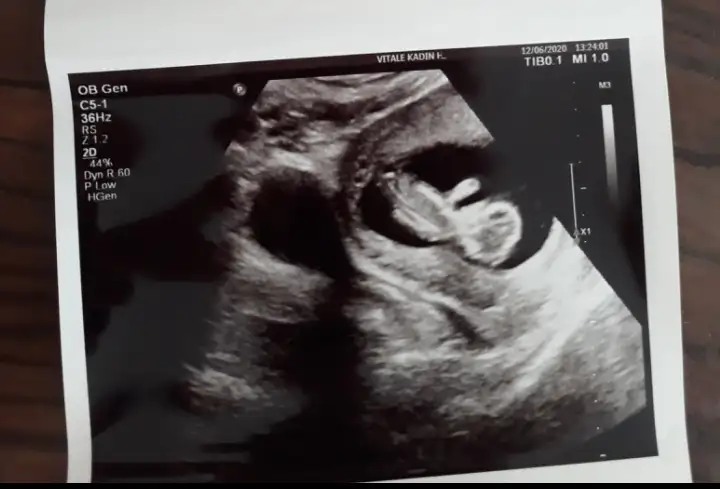

Emin olmamakla birlikte kıza benzettimBen de 12+2 haftalığım. Doktor bir tahminde bulundu ama görebilirseniz bana da tahminde bulunabilir misiniz.

Başka yok malesef ultrason. Tekrar gittiğimde atarım yine. Doktor bir çıkıntı gösterip erkek dedi ama kesin değil demişti. Ultrasonda göremedim ben de o çıkıntıyı.Emin olmamakla birlikte kıza benzettimnet değil nubu degil baş taraftan almış usg varsa başka usg paylaşın 11 hafta yada olursa 13+ hafta paylaşın

Hayırlısı olsunBaşka yok malesef ultrason. Tekrar gittiğimde atarım yine. Doktor bir çıkıntı gösterip erkek dedi ama kesin değil demişti. Ultrasonda göremedim ben de o çıkıntıyı.